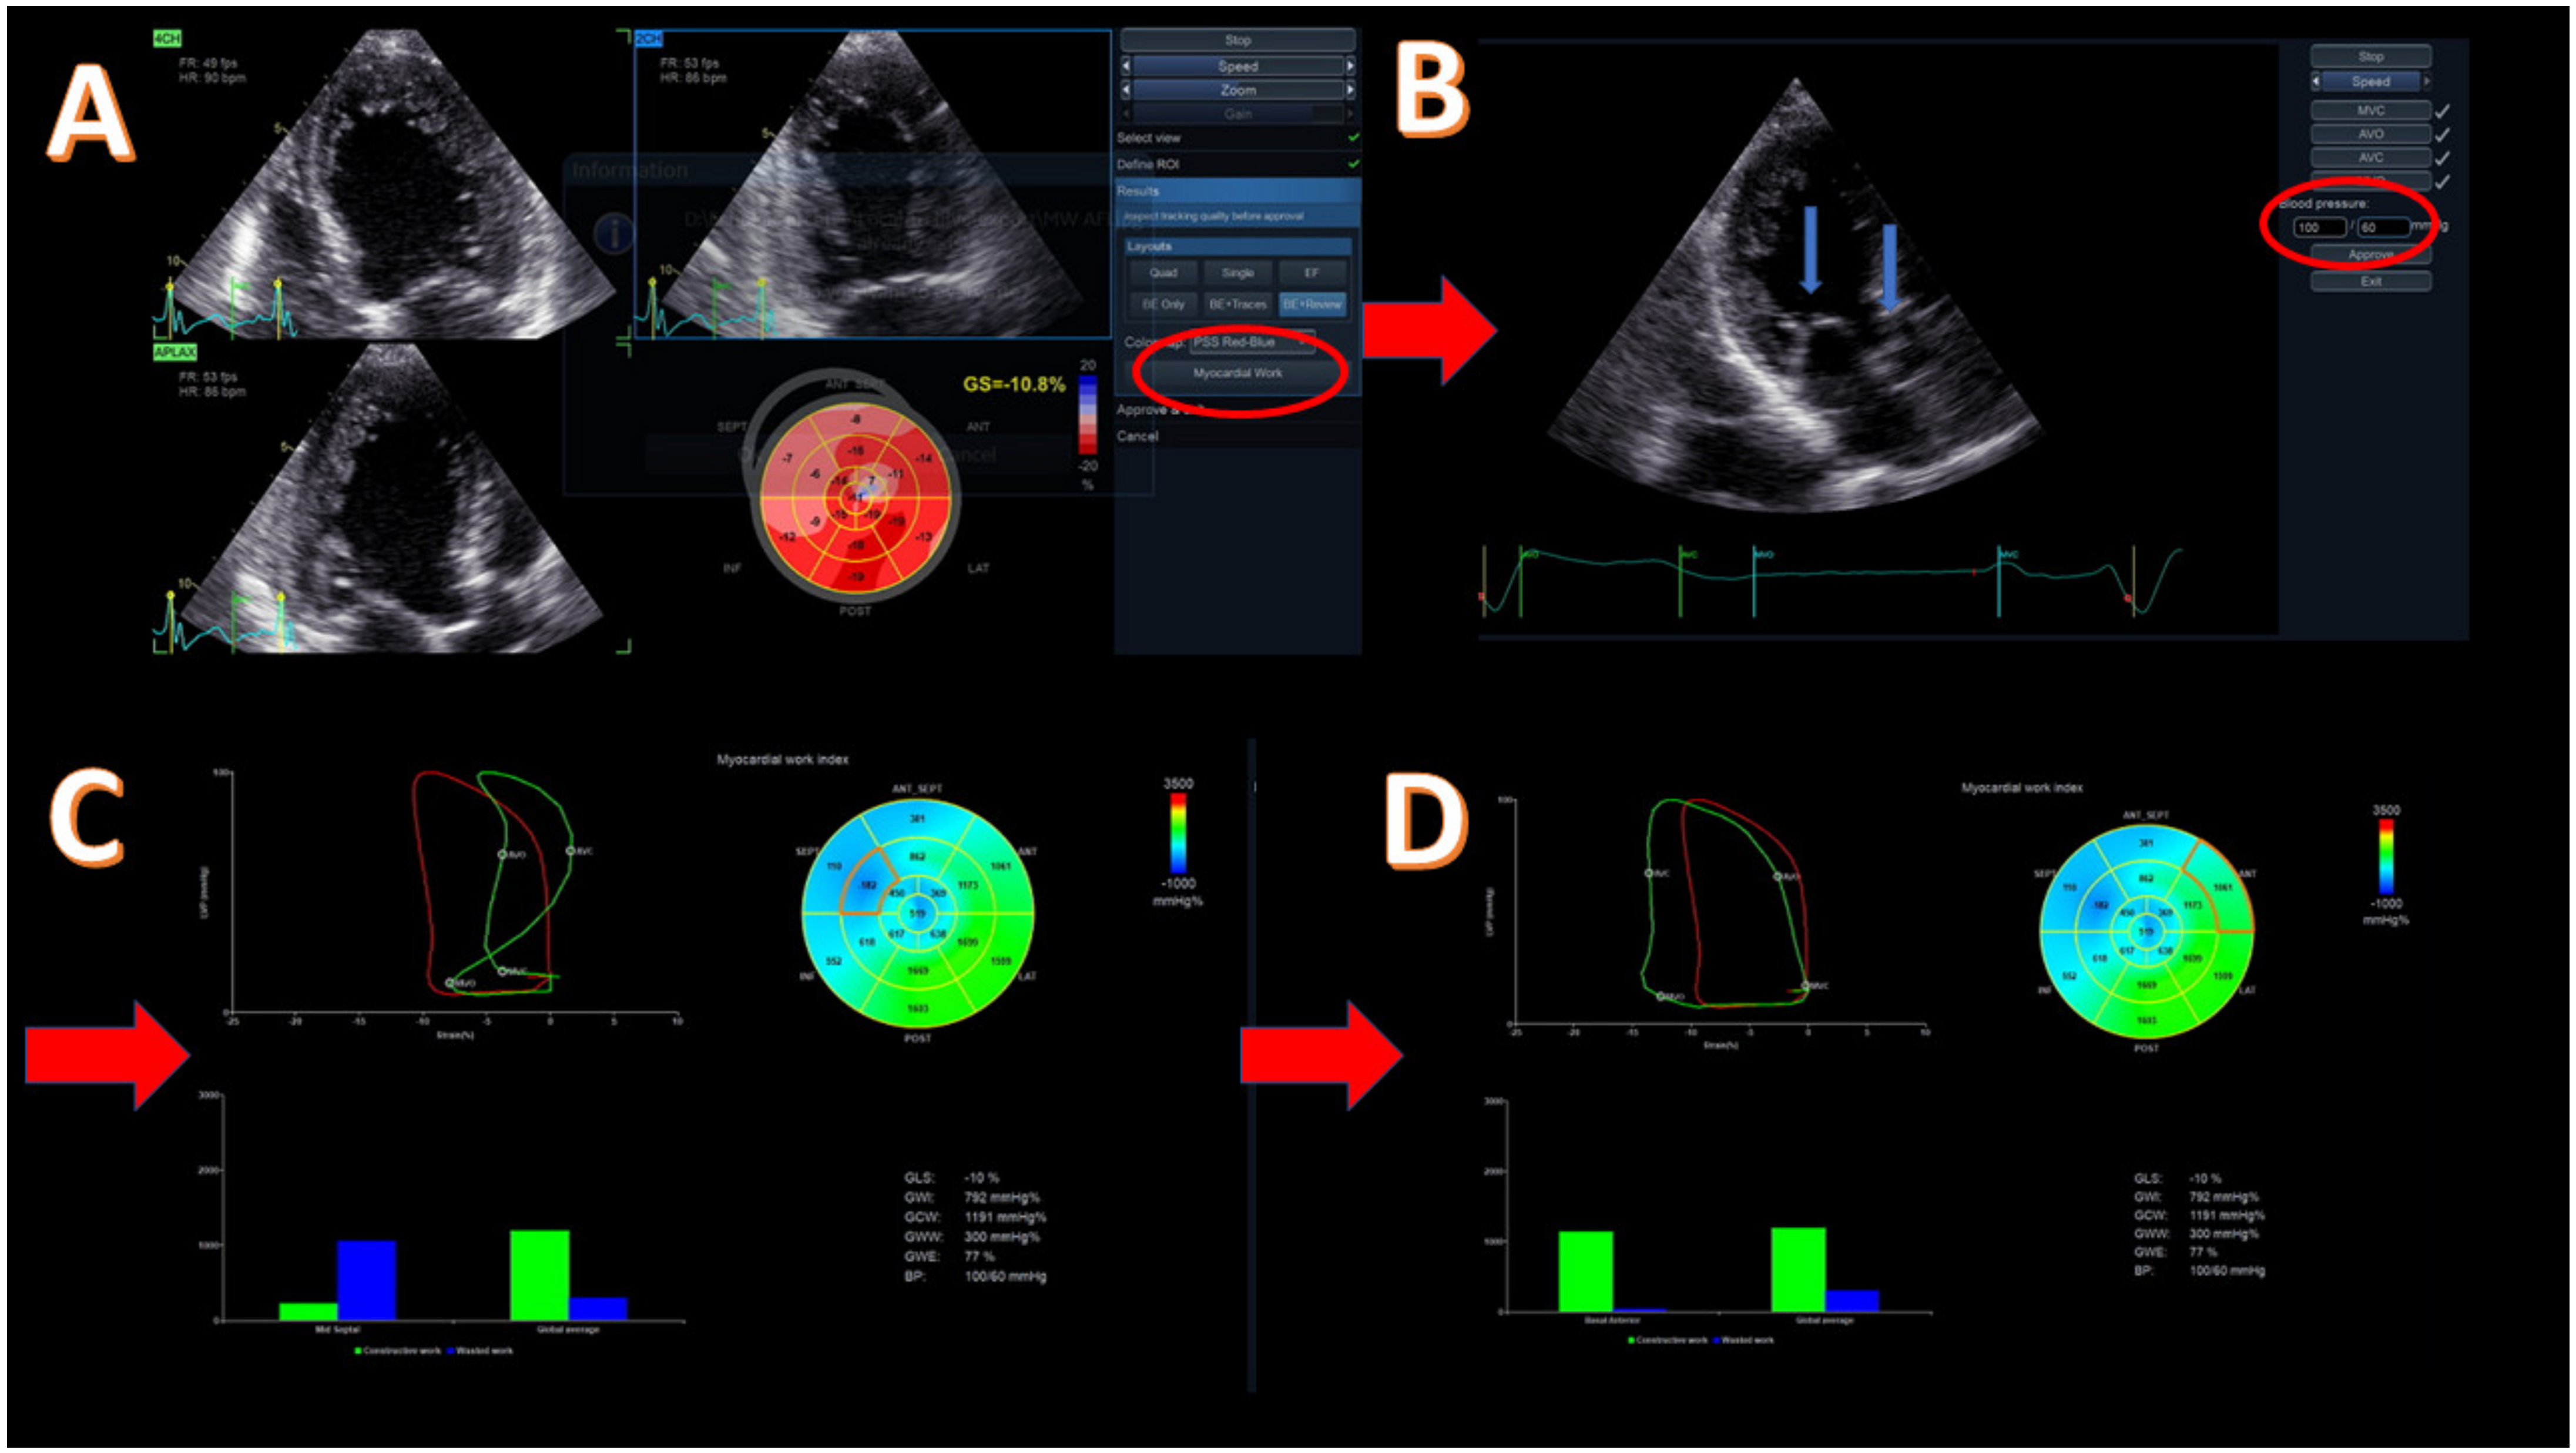

Figure 2. Methodology of myocardial work (MW) for a patient with reduced ejection fraction (EF = 30%) due to cardiotoxicity. (A) Acquisition of apical four-, two-, and three-chamber view and evaluation of global longitudinal strain (GLS) with left ventricular (LV) bull’s eye; GLS = −10.8%. The highlighted button (with red circle) moves to the next step for myocardial work evaluation. (B) Introduction of systolic and diastolic blood pressure (red circle) and confirmation of the correct event timing in apical three-chamber view. The blue arrows point to mitral and aortic valves that should be clearly demonstrated. (C) Evaluation of global values of all MW components, including bull’s eye of the work index, global pressure–strain loop (red loop), and segmental pressure–strain loop (green loop), showing a dyssynchronous mid-septum segment and bars showing the relationship between the constructive (green bar) and wasted (blue bar) segmental (left) and global work. (D) Evaluation of the same global values as in image C but with different segment for pressure–strain loop analysis and with constructive/wasted work bars. Basal anterior segment with constructive work similar to the global one. Red arrows show the next step of the methodology.